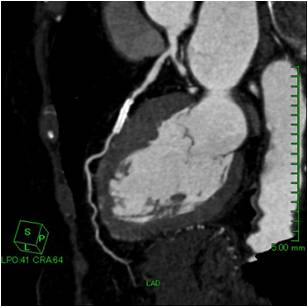

心筋梗塞や狭心症を引き起こす原因は、心臓周りを取り巻く血管(冠動脈といいます)の内部が狭くなったり閉塞したりして血液供給が不十分になり発生します。

X線CTでの心臓検査は、造影剤を腕から入れて、数秒間の撮影を行うだけで検査が終わりますので日帰り検査も可能であり、被ばくの心配等も少ないです。